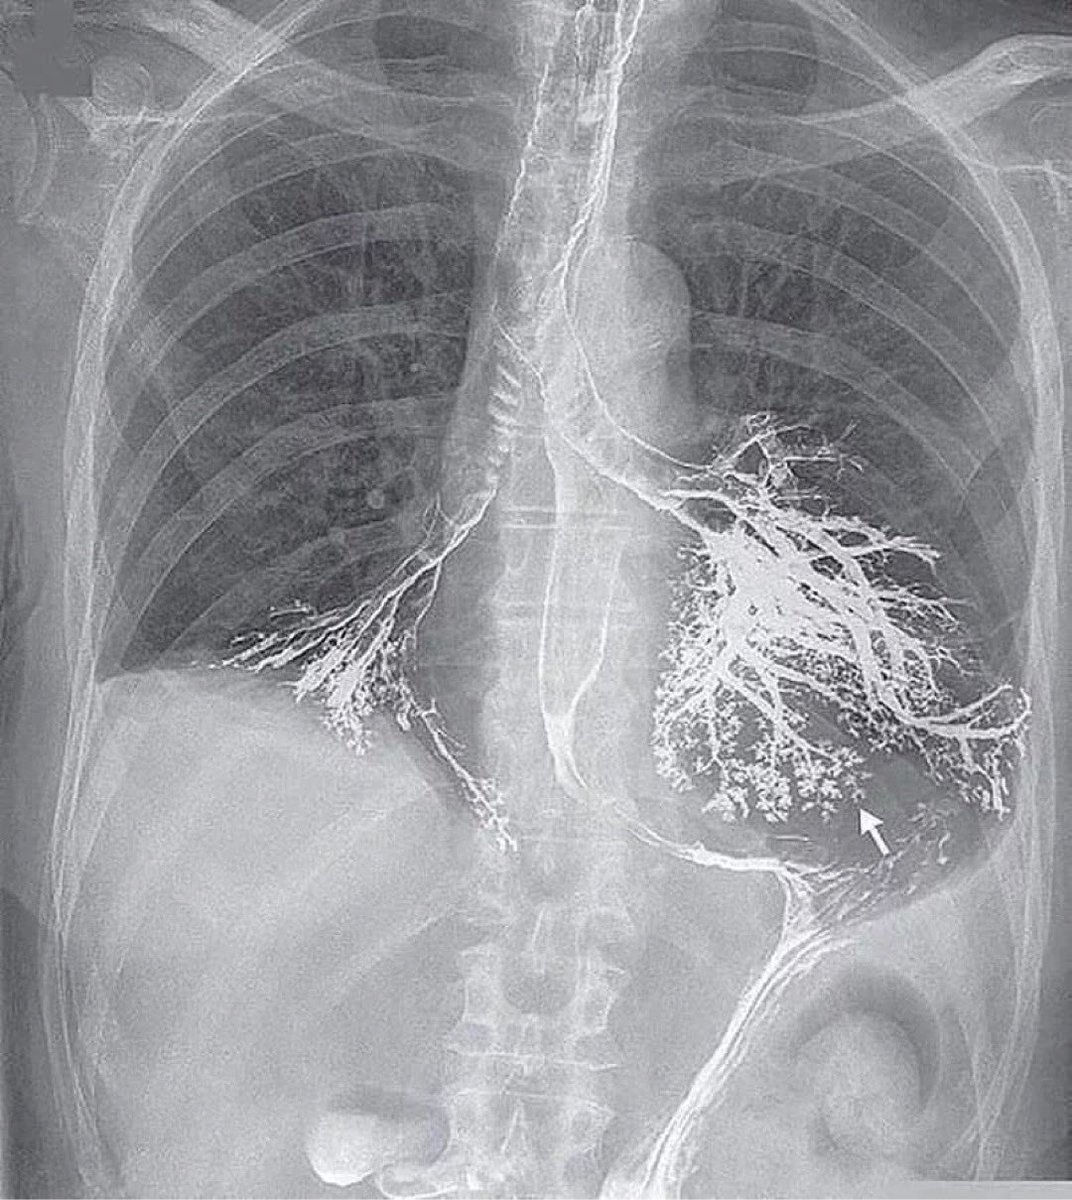

这是新英格兰医学杂志的一个病例报告

这是一个悲剧,病人是一个老爷子,他在接受消化道钡剂造影过程中将钡剂吸入气管和支气管中

胸片可看到食管和胃的轮廓及钡剂流挂,气管支气管也显影,双下肺造影剂充满管腔

通常钡剂造影用于消化道,钡剂进入肺后不易排出

病人迅速出现低氧呼吸困难,病人呼吸衰竭直至循环衰竭、心跳骤停,最终脑死亡